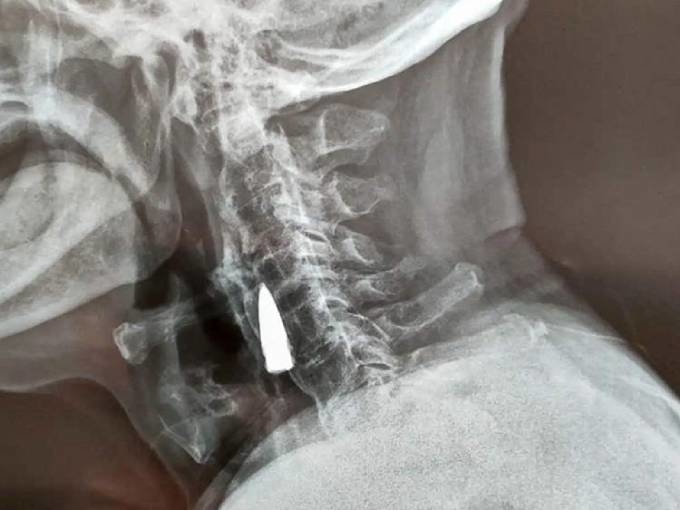

Viên đạn mắc trong cổ ông Zhao qua hình chụp x-quang. Ảnh: Oddity Central

Sau khi nghe Zhao kể về cú ngã, các bác sĩ đề nghị chụp x-quang để đảm bảo ông không bị thương nặng ở cổ. Tuy nhiên, thay vì phát hiện vết rạn xương, kết quả cho thấy có vật lạ mắc ở cổ bệnh nhân. Vật này sau đó được xác định là một viên đạn cũ.

Zhao đoán ông bị trúng viên đạn trên ở cổ năm từ năm 1944, khi băng qua một con sông. Viên đạn dường như xuyên qua bên mũi trái, qua hàm trên và làm gãy răng ông trước khi găm vào cổ. Tuy nhiên, đây chỉ là linh cảm, phỏng đoán của Zhao.

Sau khi kiểm tra phim chụp x-quang, các bác sĩ nói với ông Zhao He và gia đình rằng viên đạn nằm gần một số mạch máu lớn, và do nó không gây ra vấn đề gì cho bệnh nhân nên tốt nhất là không can thiệp.